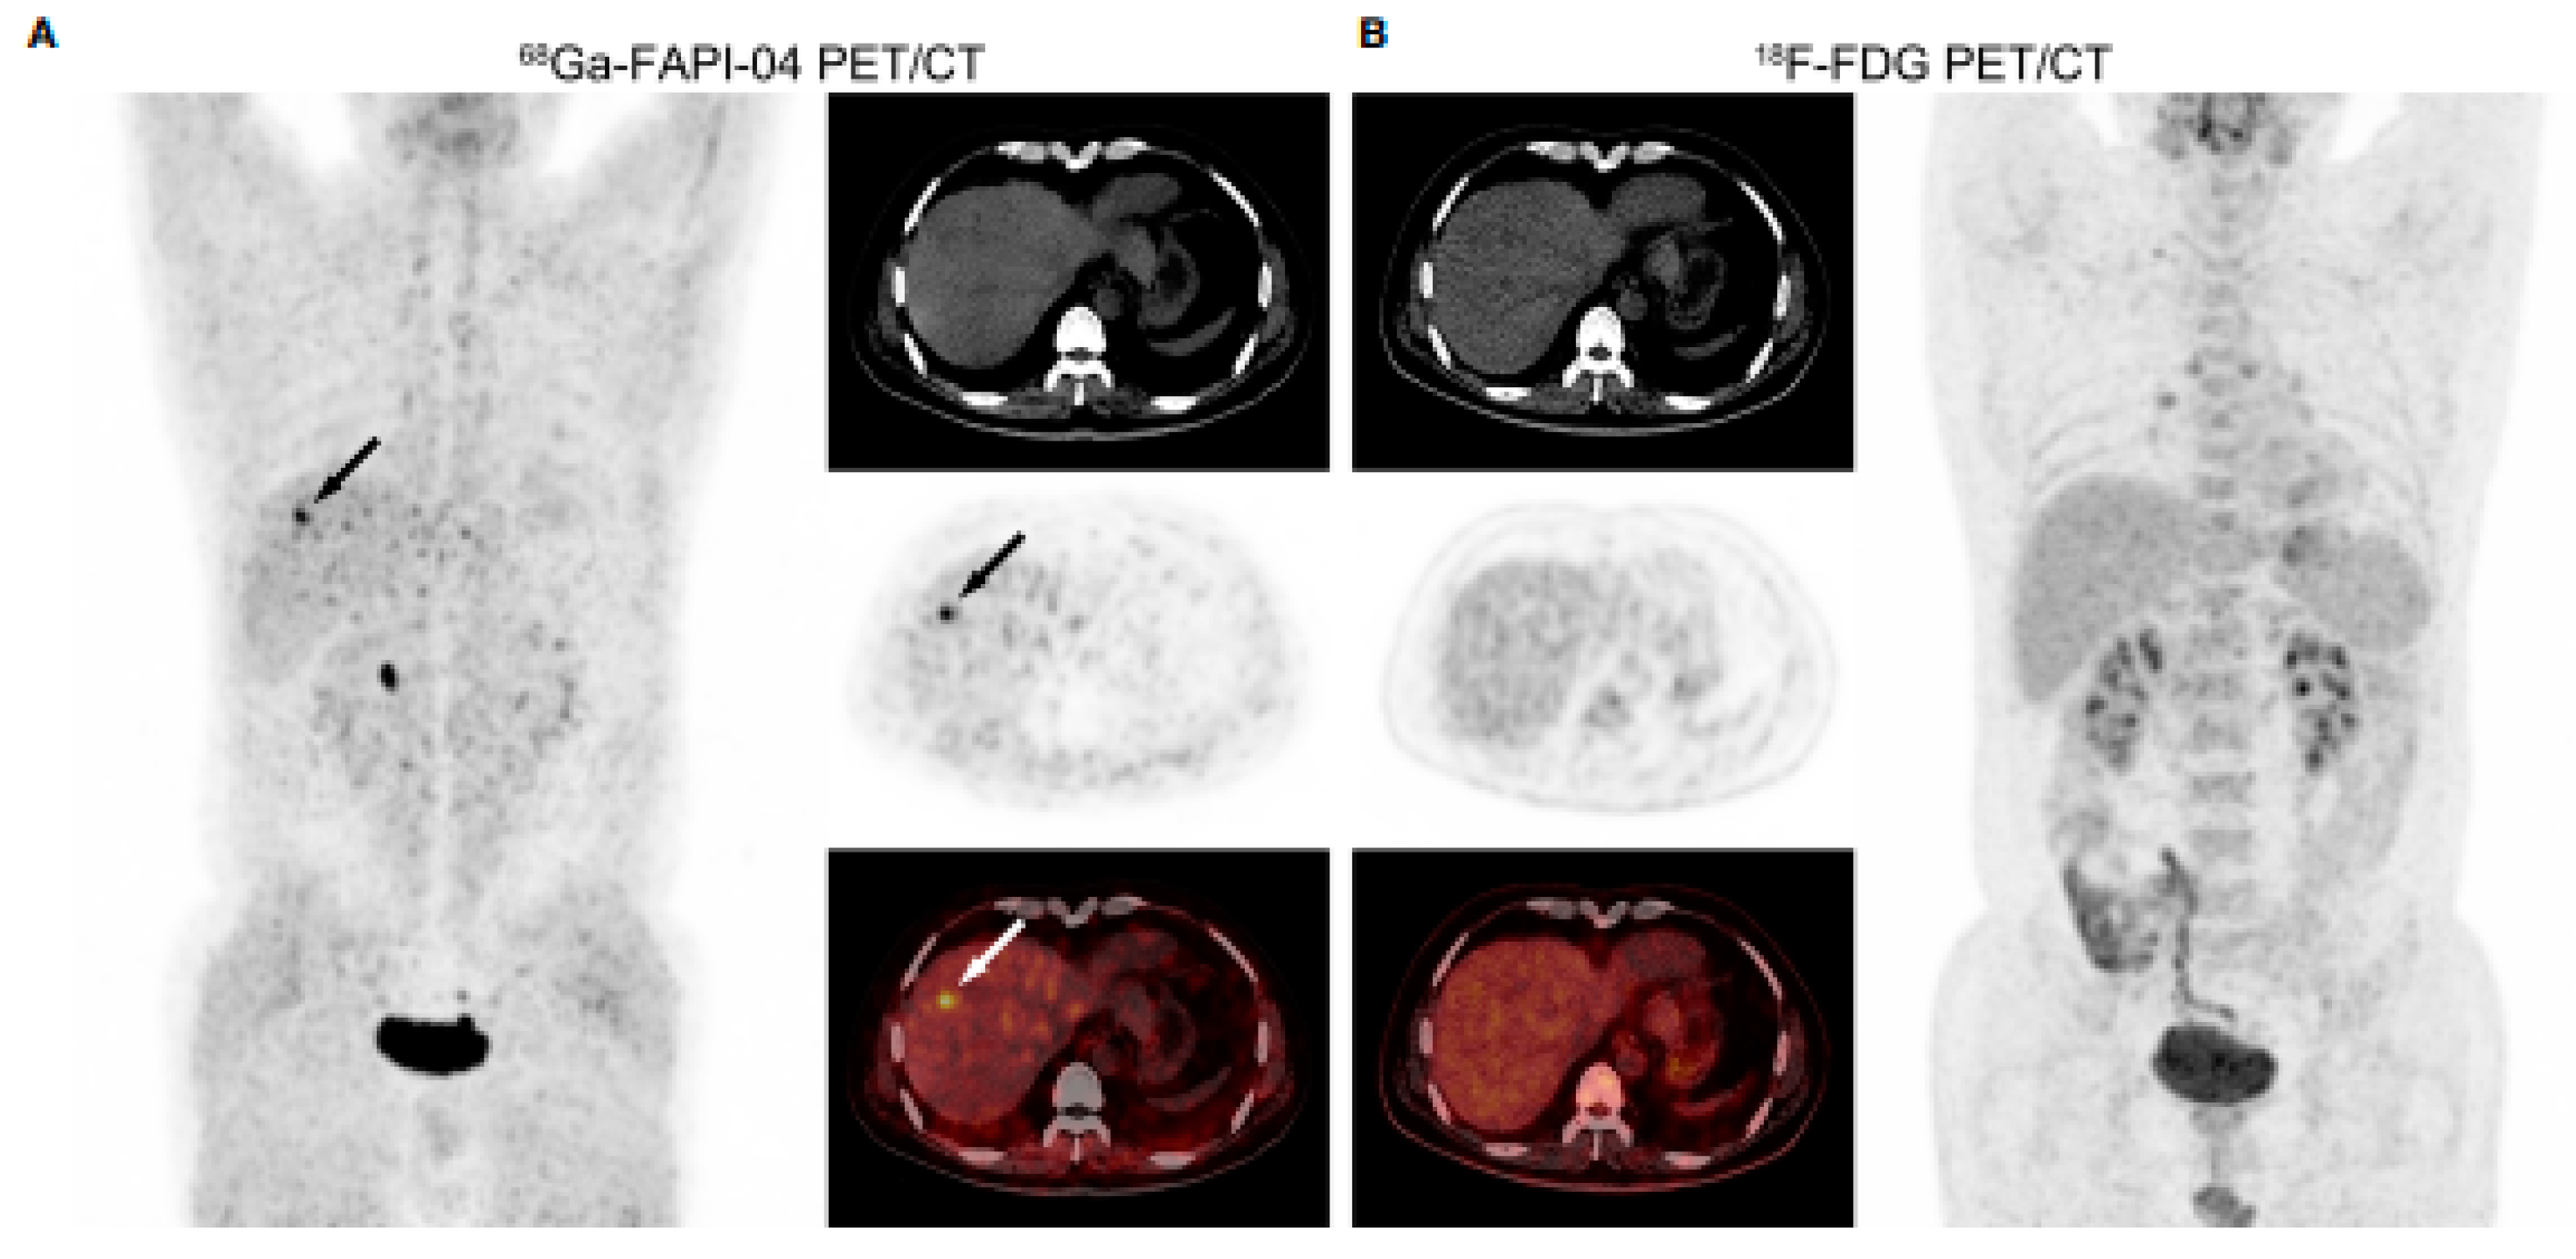

- Shi, X.; Xing, H.; Yang, X.; Li, F.; Yao, S.; Zhang, H.; Zhao, H.; Hacker, M.; Huo, L.; Li, X. Fibroblast imaging of hepatic carcinoma with 68Ga-FAPI-04 PET/CT: A pilot study in patients with suspected hepatic nodules. Eur. J. Nucl. Med. Mol. Imaging 2021, 48, 196–203. [Google Scholar] [CrossRef] [PubMed]

| Wang H, et al. [31] 2021, China | Retrospective study | 68Ga-FAPI-04 vs. 18F-FDG | 29 patients (24 m) HCC | 68Ga-FAPI-04 was more sensitive than 18F-FDG in detecting small HCCs (≤2 cm) and well- or moderately differentiated HCCs (both p < 0.005), but there were no significant sensitivity differences in the detection of HCCs > 2 cm and poorly differentiated or undifferentiated HCCs (both p > 0.05). |